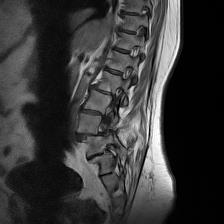

Slipped L$ Disc Image Published May 27, 2017 at 224 × 224 in Tiny Birdwatching and Back Doctor Visit Next → Slipped L$ Disc Image Slipped L$ Disc Image 1 Share this: Email a link to a friend (Opens in new window) Email More Share on Pinterest (Opens in new window) Pinterest Like Loading...